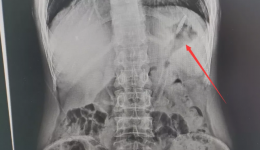

• 医生在他的胃里取出长18cm的牙刷......

医生在他的胃里取出长18cm的牙刷......

你能想象,胃里有18cm牙刷的样子吗?近日,一男子因吞食牙刷,被紧急送往广西壮族自治区桂东人民医院。医院消化内科接诊医师陈思羽在患者和家属断断续续地描述中,了解到患者患有精神疾病,在无人看管时误吞食了牙刷。在明确病情后,陈医师立即为小...

发布时间:2021-05-19|来自:管理员